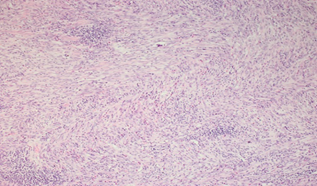

Introduction: Colorectal cancer (CRC) is one of the most common cancers worldwide. Individuals with elevated lipid levels are at risk for developing cardiovascular disease as well as cancer. Sterol regulatory element-binding protein transcription factors (SREBPs) are inducers of lipid synthesis. It’s reported that SREBP1a and its target gene FASN are metabolic oncogenes. Their suppression leads to decrease lipogenesis and reduce proliferation and survival of CRC. This study focuses on the expression of SREBP1a and FASN proteins in colorectal adenoma and carcinoma and correlates their expression with the available clinicopathological data.

To citation of this article: Dr. Aya Abuzeid, Egypt,Role of sterol regulatory element-binding protein 1a and fatty acid synthase in colorectal carcinoma, Global Journal of Pathology & Laboratory Medicine